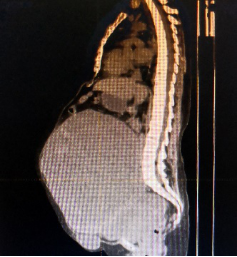

腹部巨大包块影像检查

都说人到中年易发福,但对王女士来说隆起的肚子却是她八年来日夜焦心的“负担”。2013年,她的腹围突然增大如怀胎六七个月,医院检查结果考虑盆腔内恶性肿瘤可能,本应该尽快手术,但肿瘤包绕腹主动脉,多家医院就诊后都表示手术难度大,很可能“开得了刀,下不来台”。王女士被迫开始了姑息治疗,八年来吃药、反复抽胸水,略有好转又有反复,成了她无法摆脱的负担。所幸的是,不久前,上海市第十人民医院妇产科团队在仔细评估后,认为患者还有治疗机会,并成功实施手术拆除了王女士腹部这颗“不定时炸弹”。

入院后,团队对王女士进行了详细的身体检查,一方面排除血栓的可能,并予以低分子肝素对症治疗,另一方面考虑到患者左侧胸腔积水,请胸外科进行胸腔穿刺引流,并由介入科对盆腔的巨大包块进行造影检查,明确了包块血供不是来源于大血管,麻醉科、输血科、SICU等科室进行了多学科会诊,充分做好了手术准备。